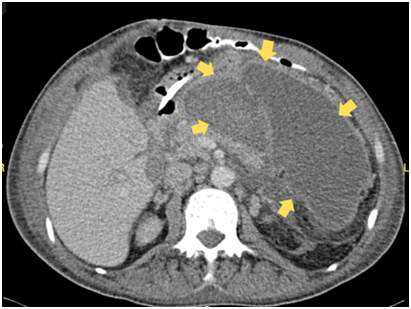

A 49-year-old male patient, with previous history of splenectomy, chronic renal failure, and left nephrectomy, is admitted due to abdominal pain, predominantly in epigastrium, of 8days associated with multiple emetic episodes and febrile syndrome. On arrival, a computed tomography (CT) scan was performed reporting acute cholecystitis requiring an open cholecystectomy based on the previous interventions presenting a surgical challenge. During the post-operative period, patient had a poor clinical progression leading to a second surgical intervention where a hemoperitoneum of approximately 1500cc was discovered, without proper visualization of the source of bleeding. This led to packing of the abdomen and closure of the incision. Posterior to this, multiple surgical peritoneal lavages were performed until complete closure of the abdomen wall was achieved and the bleeding resolved. However, the clinical course continued to be torpid, whereby a second abdominal CT scan was used, discovering a gastro-hepatic ligament abscess of 15x6x9cm in size with an approximate volume of 450cc (Figure 1) (Figure 2). Given the multiple previous surgical interventions and high risk of a “hostile” abdomen, a retroperitoneoscopic drainage as the ideal treatment.

Figure 1&2 Abdominal computed tomography (CT) scan. The arrow represents the fluid collection of 15x6x9cm with an approximate volume of 450cc.